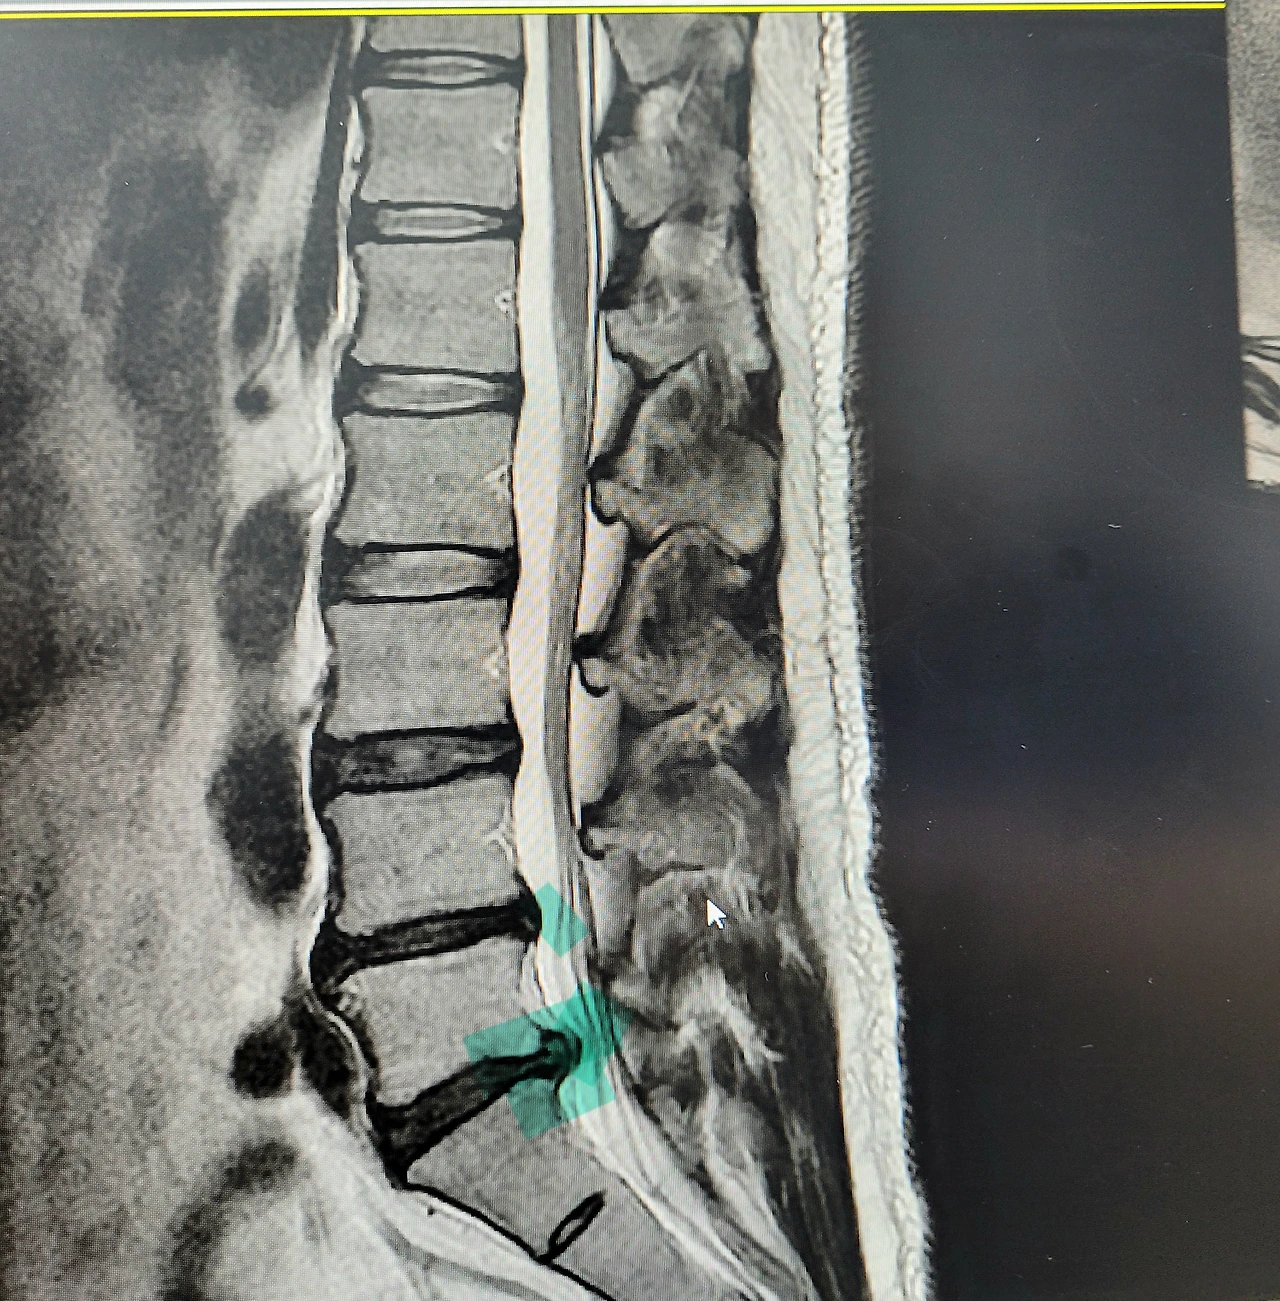

그래도 필라테스를 수년간 꾸준히 해와서 버텨왔는데 아버지 장례와 밀린 일 처리를 거치면서 디스크가 터지고 말았습니다. (디스크 추간판 탈출-척추 사이에 있는 디스크가 과도한 압력을 버티지 못하면서 수핵이 터져서 후방외측으로 삐져나와서 신경을 눌러 나타나는 증상)

L5-S1 부위/ 앞쪽으로는 광활한 복부지방 영역이...